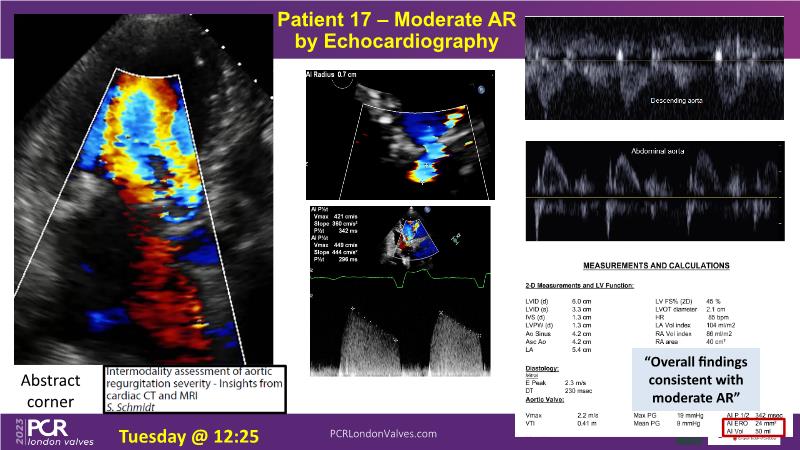

- To understand the challenges of imaging for aortic regurgitation and how it can lead to underdiagnosis